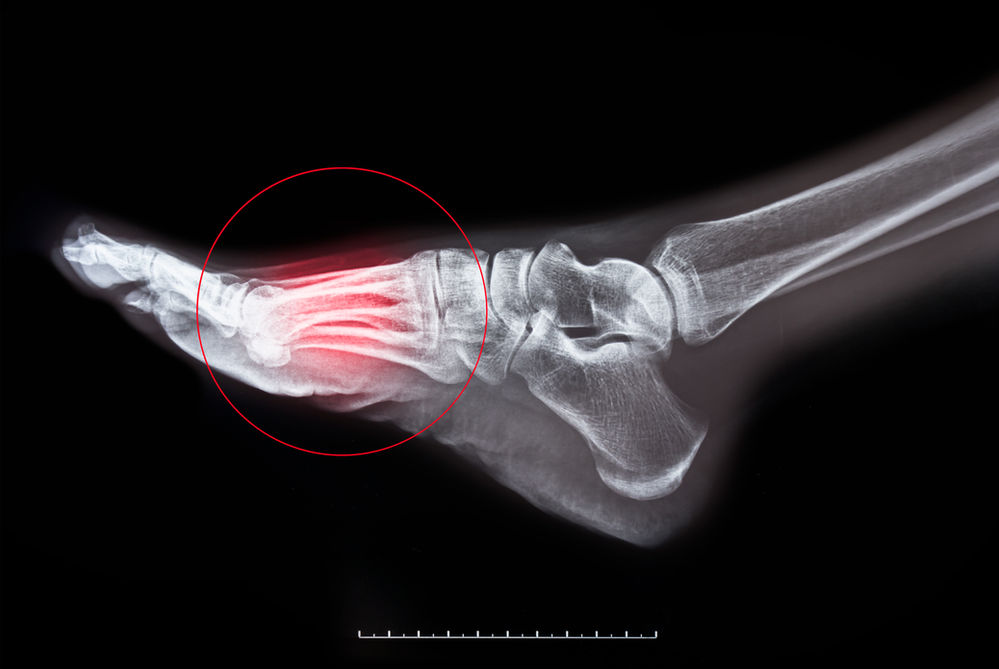

Osteoporosis bone fractures leg. 3d illustration of human foot bones on Osteoporosis And Foot Fractures In fact, bone loss in the foot elevates your overall risk for stress fractures. The most common first sign of osteoporosis is often an unexpected fracture, usually in the wrist, hip, or spine, following a. That makes the bones of someone with osteoporosis inherently weaker, which leaves them more prone to injury. The effects of osteoporosis of the foot may. Osteoporosis And Foot Fractures.